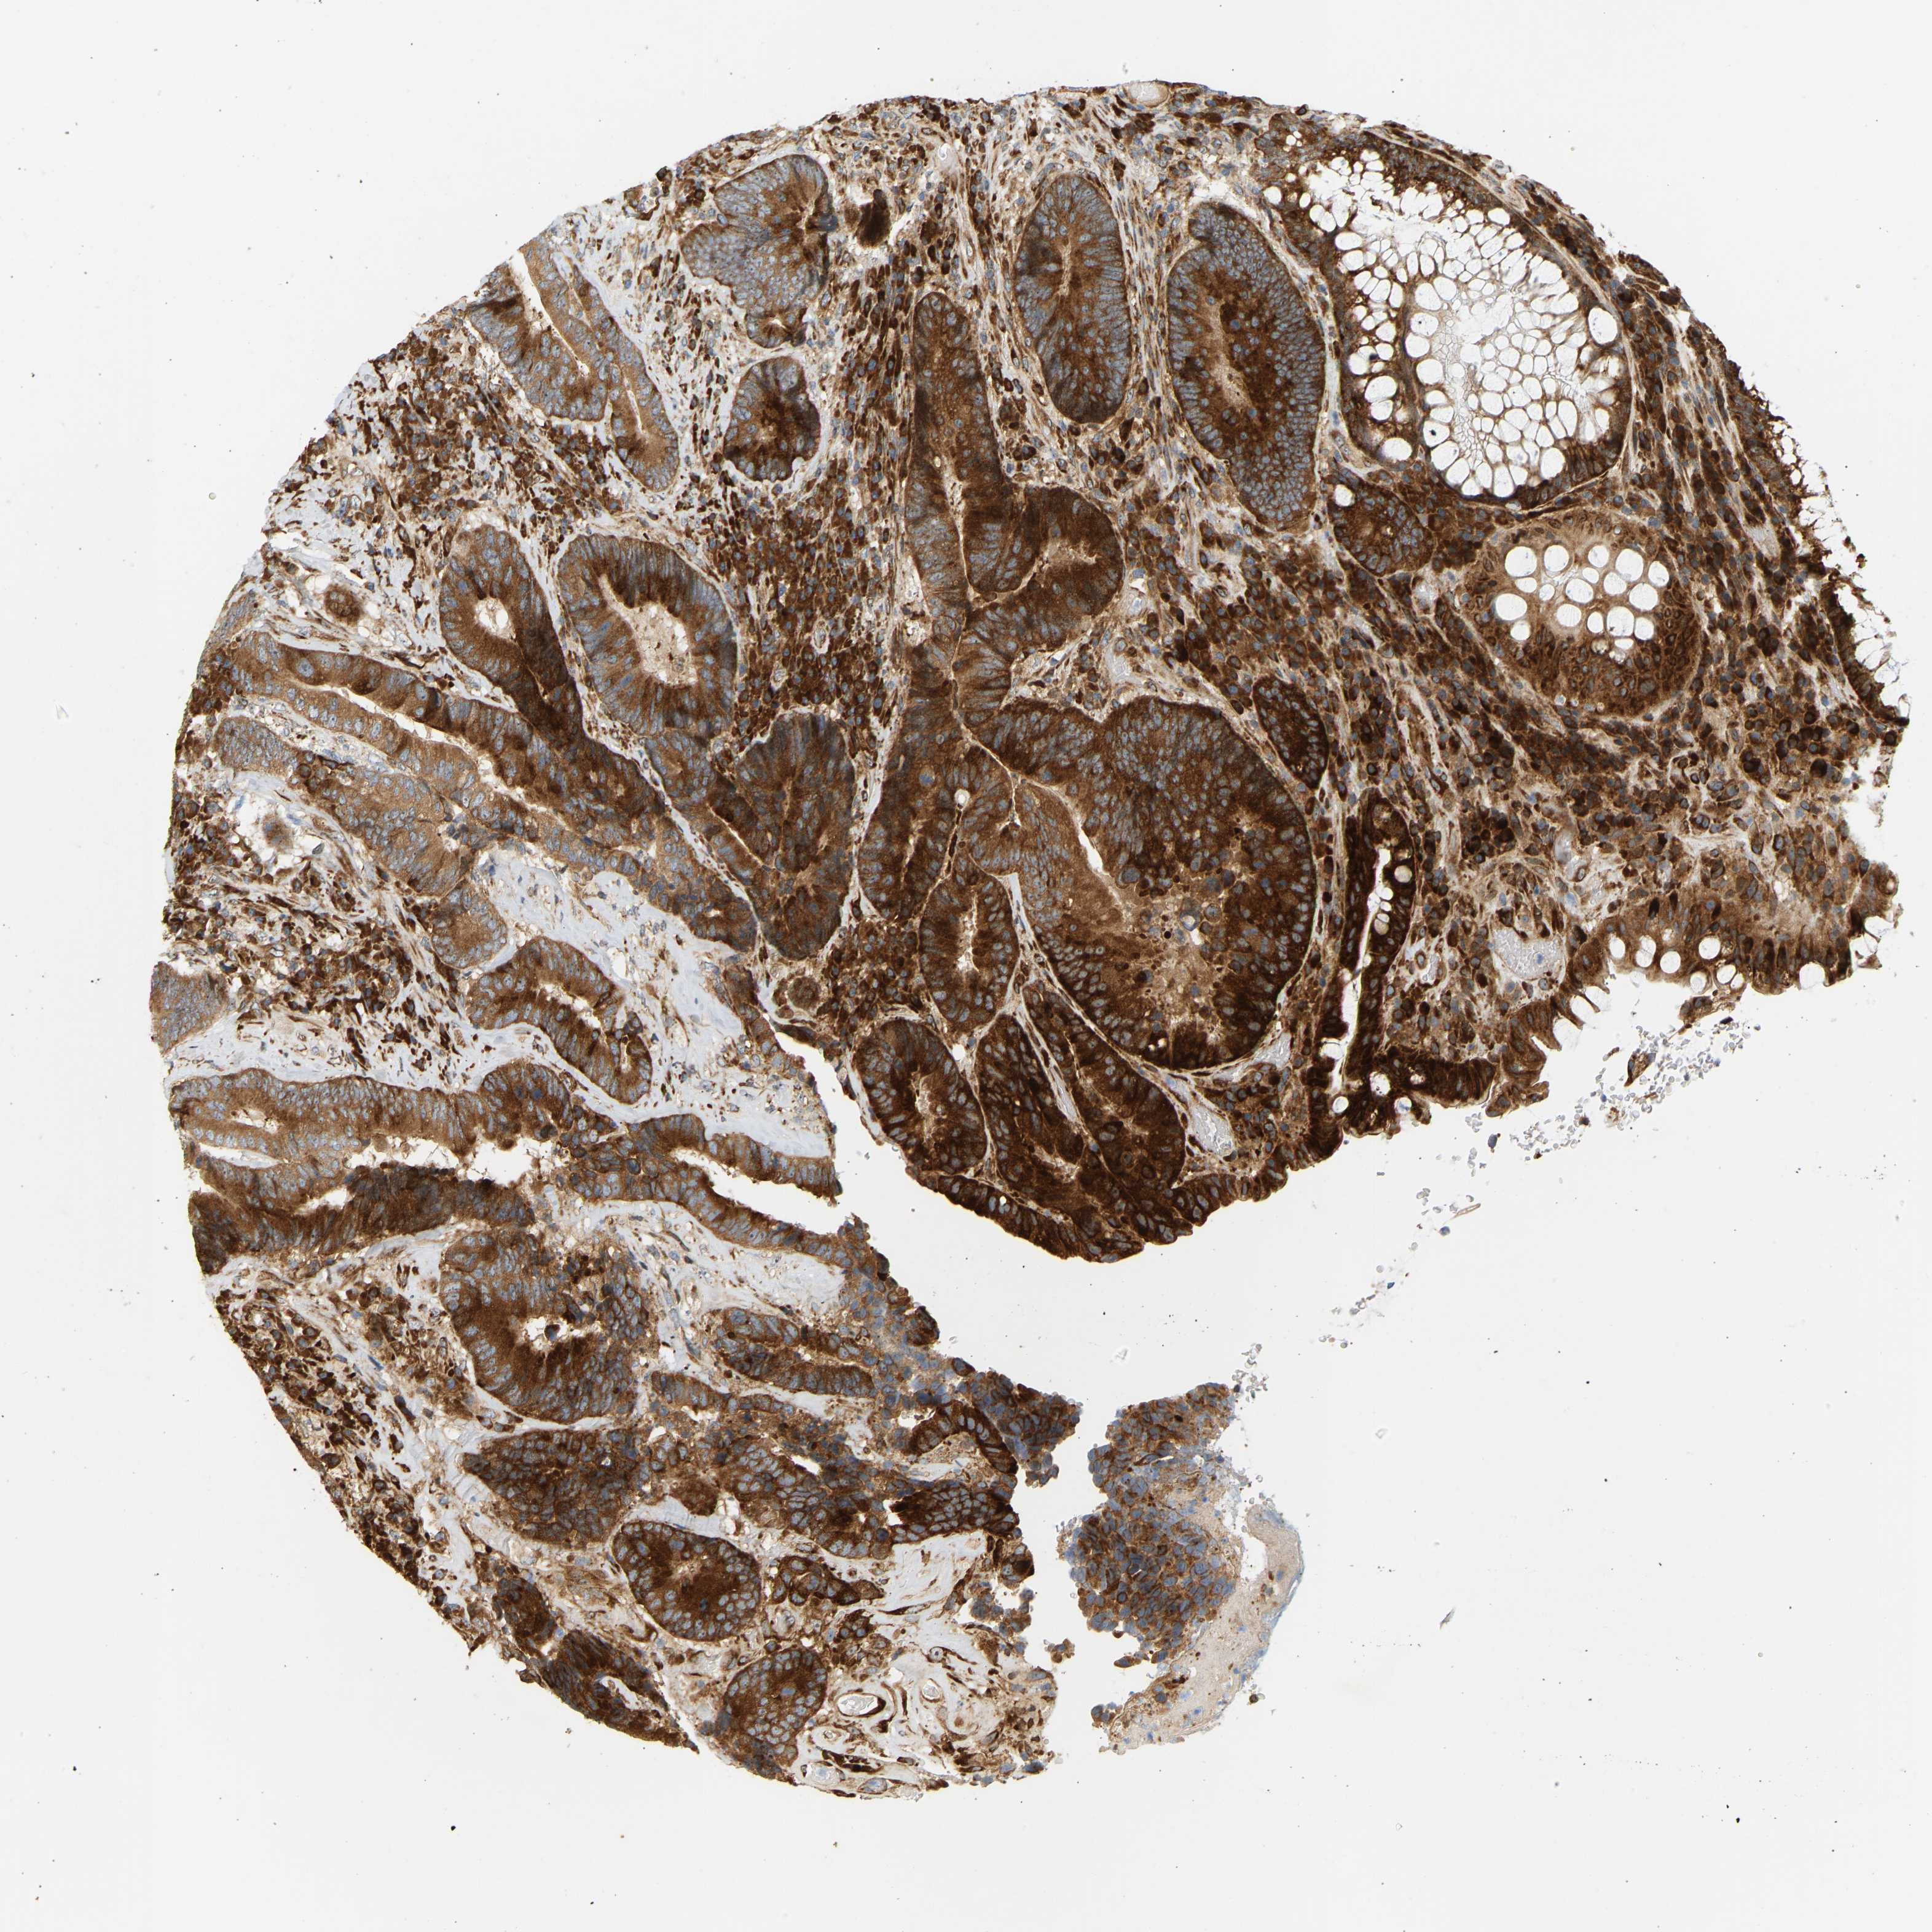

CANCER COLORECTAL CANCER Show tissue menu

ANTIBODIES

AND

VALIDATION